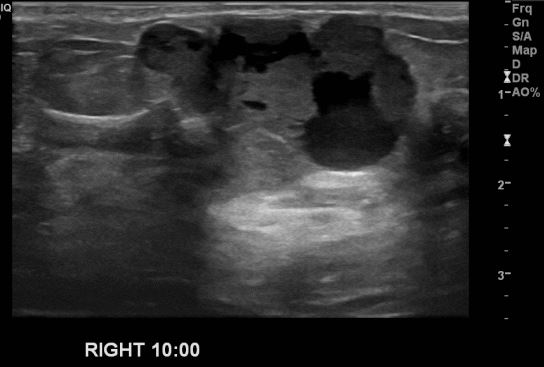

건강검진상 이상 소견으로 내원하신 40대 여성 분으로 우측 10시 방향의 의심스러운 혹

조직검사 시행하여 우측 유관암 진단 되었습니다.